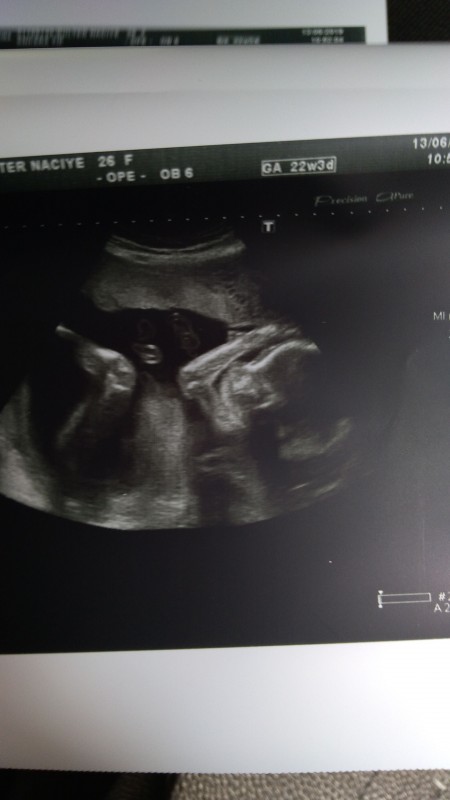

Haftada artık bebeğin cinsiyeti net bir şekilde görülebilecektir. Ancak 16 haftadan sonra bebeğin duruşu uygun olmadığı için muayenede görülemeyebilir. Renkli doppler ve biyofizik profil i̇nceleme. Haftalarda ultrasonla cinsiyetin görülebilmesi daha uygun olacaktır.

Gebeliğin başlamasıyla en fazla merak edilen konulardan biriside bebeğin cinsiyeti olmaktadır. Genel olarak bebeğin cinsiyeti erkek ise yanılma payı daha düşük olur. Gebelik süreci bilinen üzere sancılı ve merak uyandıran uzun bir dönemdir. Bebeklerin cinsiyet konusunda ne olduğunun belli olması için ayrıntılı tarama testi yapılmalıdır.

Hatalı cinsiyet tahmini sevgili anneler hep duyuyoruz ya doktor aylarca kızın olacak dedi ama bir baktık ki oğlan doğdu ya da tam tersi. Cinsiyet öğrenildikten sonrasında hazırlıklar başlar. Bazı durumlarda erkek bebeklerin eğer bacakları kapalı arkadan bakıldığında kız bebek diye. Ayrıntılı ultrason cinsiyet yanılması yaşayanlar ikinci gebeliklerinde yeniden yaptırsın mı.